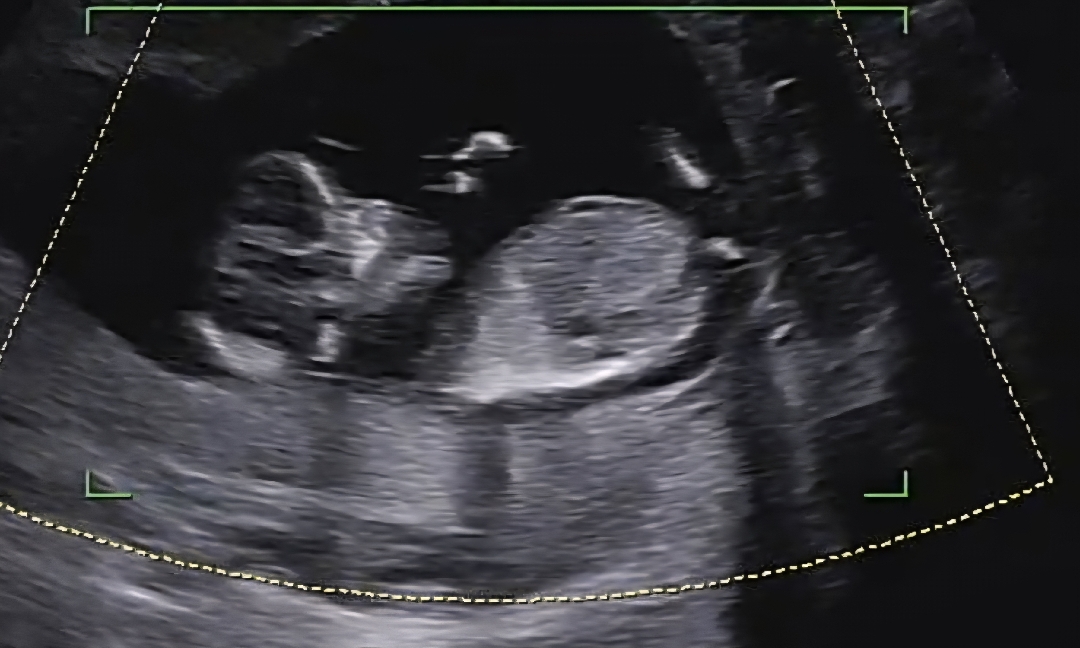

딸일까요 아들일까요??

12주차 입니다 각도법 고수님들 댓글달아주세요~